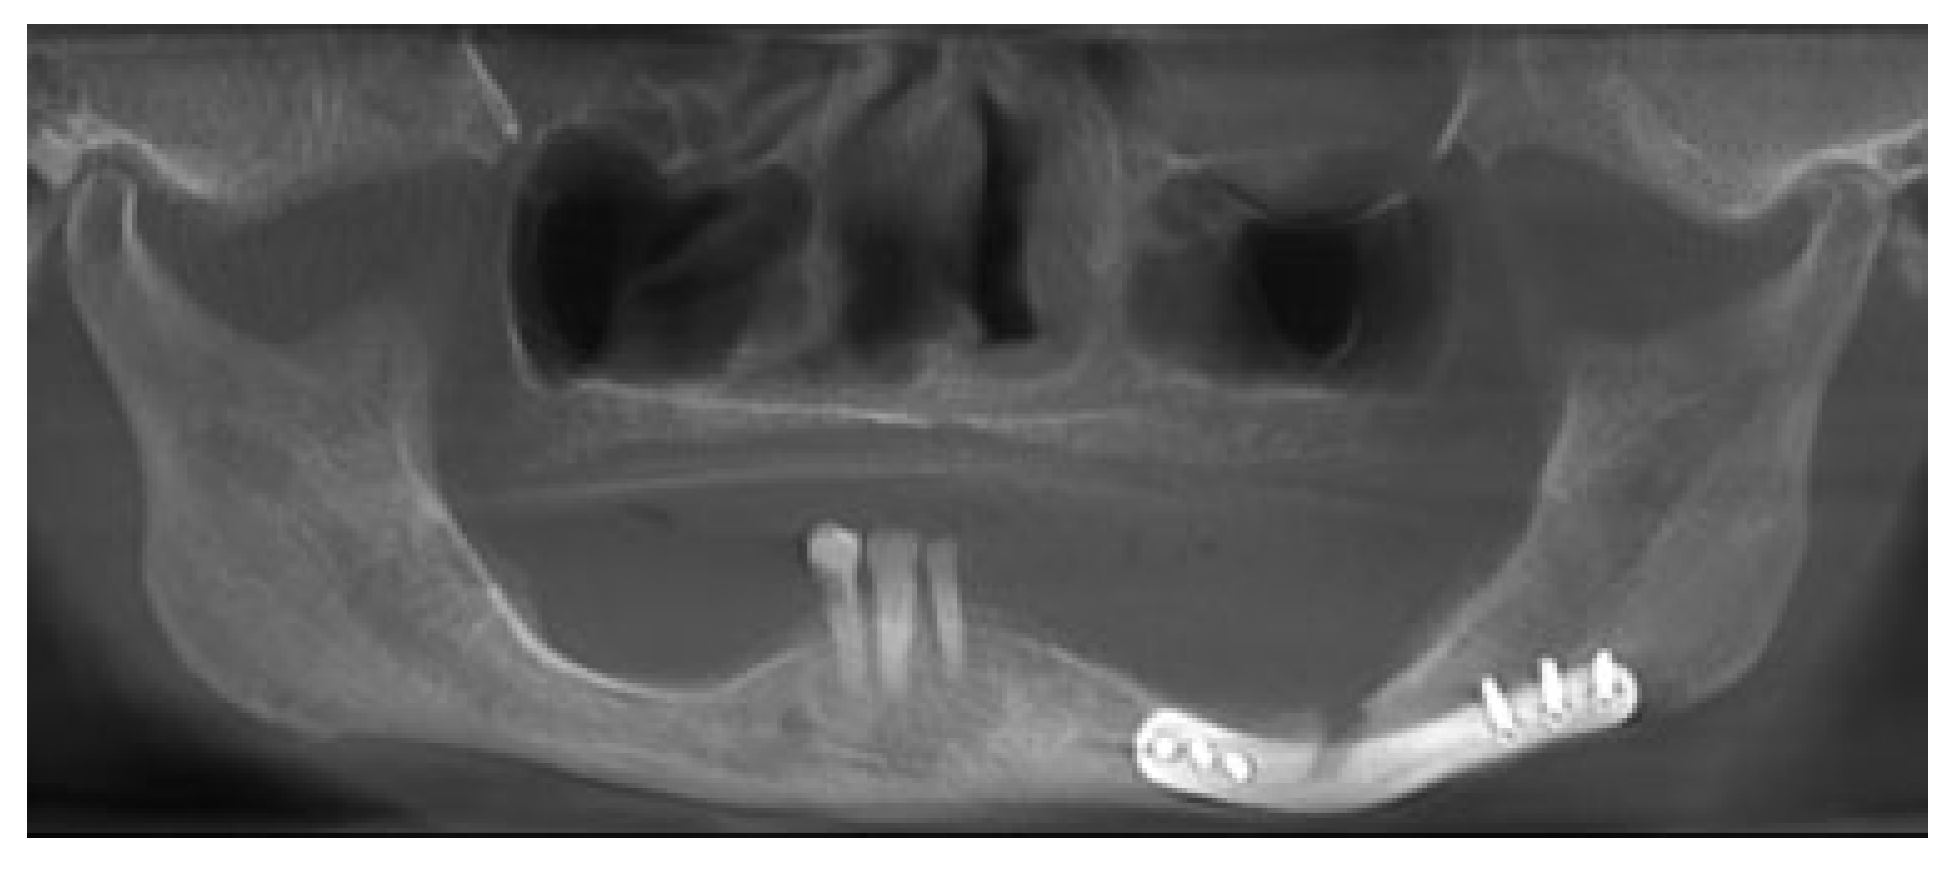

An 81-year-old woman had a fall and was diagnosed with a nondisplaced left mandible fracture. She was unsuccessfully treated with a soft diet by another oral and maxillofacial surgeon and upon repeat imaging had displacement of her fracture. She was then referred to the authors for management of her injury. Her past medical history was significant for systemiclupus erythematosus (SLE), nephritis, and a right lung mass, for which she refused workup. A CBCT was taken which showed a displaced fracture of the left mandibular body (Figure 8). VSP was again arranged using PRO PLAN. The fracture was virtually reduced and a patient-specific 2.0 mm reconstruction plate was fabricated (Figure 9, Figure 10 and Figure 11). The patient was taken to operating room and a submandibular approach was used for exposure of the left mandible. The reconstruction plate was applied after reduction and debridement of the fracture site and secured with bicortical locking screws (Figure 12). The incision was closed in layered fashion. The patient was discharged home the same day. A postoperative panoramic radiograph showed adequate reduction of the fracture (Figure 13). She went on to heal well without complication and was last seen at 6 months postsurgery.

Figure 8. Case 2 after unsuccessful treatment of left atrophic mandible fracture with soft diet.